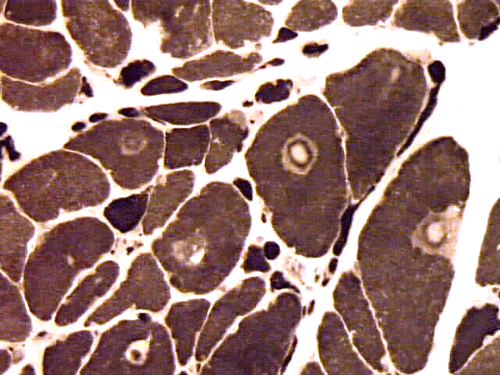

On hematoxylin-eosin stained sections, there is an increased variation of fiber diameter with many atrophic fibers intermingled with fibers of normal caliber. There is no evidence of fiber grouping or perifascicular atrophy. No inflammatory cells are present. There is also mild interstitial fibrosis (Panel A). On higher magnification, many fibers have a round concentric structure (Panel B). Irregular, centrally located depositions are also identified on modified Gomori's trichrome. The concentric nature, however, is not as obvious as in the hematoxin-eosin stained sections (Panel C). Type I and II fibers are not clearly separated in the ATPase preparation at pH 9.4. This is a common situation in chronically ill muscle (Panel D). The type I fibers are unusually dark. There is an increase in the proportion of type I fibers. The atrophic fibers are usually type II fibers. The concentric lesions are found predominantly in type I fibers (Panel E). There is an increase in PAS staining which is consistent with increased glycogen storage (Panel F). No increase in lipid content is demonstrated by oil red O (Panel G). On NADH-TR reaction, the concentric structures appear to have a clear central core that is devoid of enzymatic activity, a rim with intense enzymatic activity and a surround zone with relatively normal reactivity. These features are classic for target fibers (Panel H and I). No deficiency of laminin-2 (merosin) (Panel J) or dystrophin (Panel K) is demonstrated by immunohistochemistry. The central lesions are also immunoreactive for both laminin-2 and dystrophin. Immunohistochemistry for desmin demonstrate a core of strong immunoreactivity and also strong reaction in the sarcoplasmic membrane (Panel L and M). The target structures are also well demonstrated on semithin sections (Panel N). On electron microscopy, z-disc streaming is a common finding and they are often admixed with a substantial amount of dense granular electron dense substance (Panel O and P). There are also numerous cytoplasmic bodies characterized by radiating intermediate filaments (spheroid bodies) (Panel Q and R).